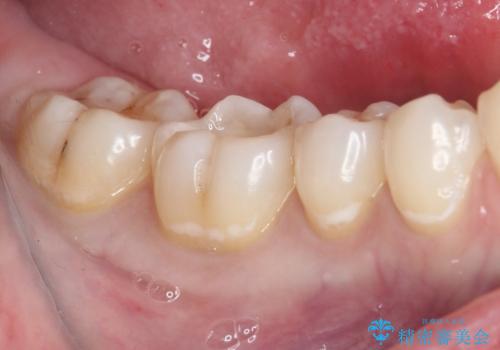

むし歯治療した歯にセラミックを入れたい セラミックインレー修復

- 他院にてむし歯の治療をし、当院にてセラミックを入れたいとのことで来院された患者様です。

むし歯がないか確認し、セラミックインレーにて修復することとしました。

セラミックインレー装着時には、唾液の侵入を防ぐために、ラバーダム防湿を行いました。

見た目、噛み合わせともに満足していただけました。

ラバーダム防湿を行い、セラミックの接着をすることで、唾液や血液などの接着阻害因子を排除することができます。